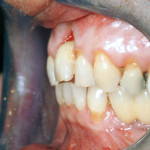

Rigenerazione ossea orizzontale e gestione dei tessuti molli in una zona estetica

La chirurgia implantare è diventata un trattamento comune nella pratica quotidiana degli studi odontoiatrici in relazione al fatto che la sostituzione di denti compromessi...